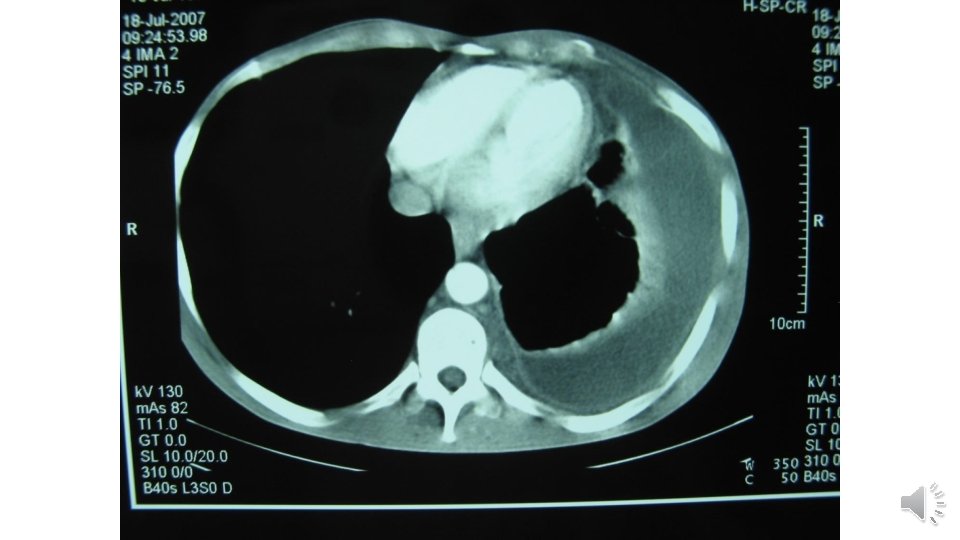

Lung CT scan